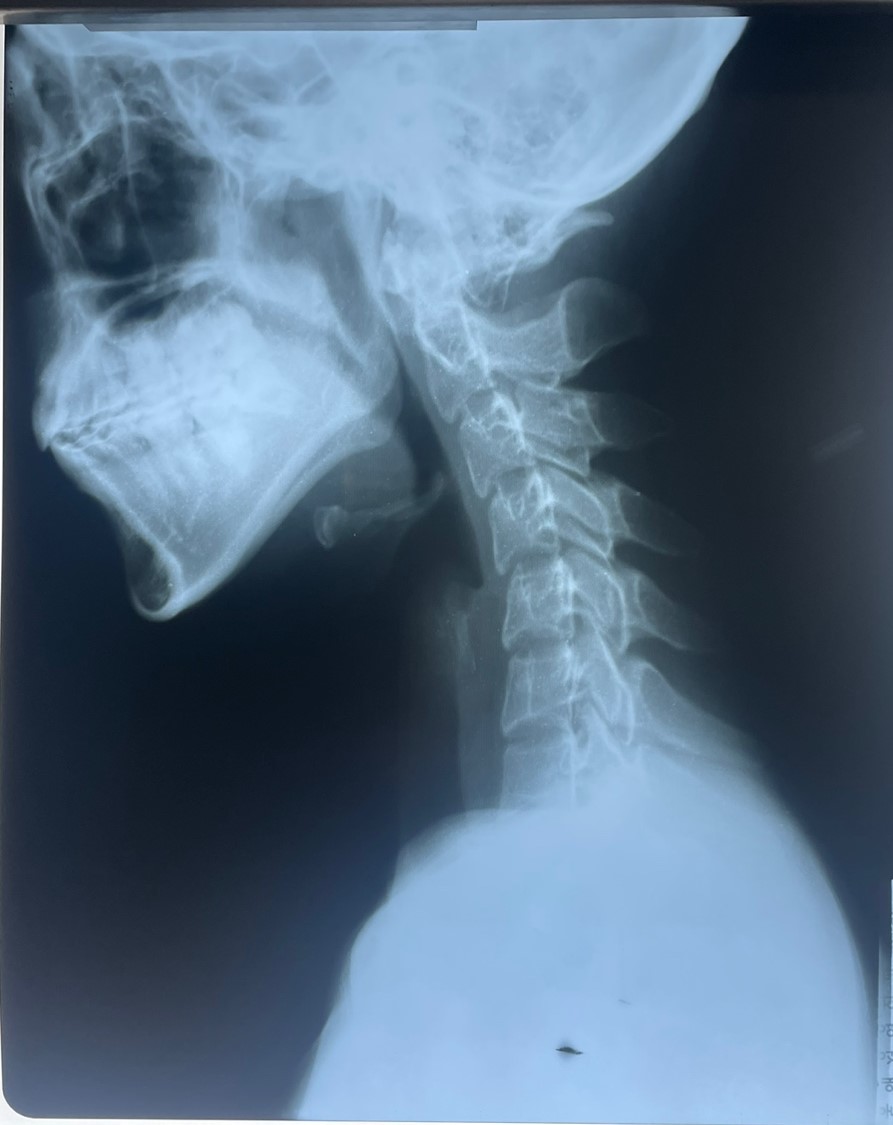

사경증 환자의 목을 X-ray로 보면 심한 역커브, 기울어져 있는 목, 들어져 있는 목 등이 복합되어 있는 것을 볼 수 있습니다. 경추가 앞으로 꺾이면서 옆으로 휘어있으면서 틀어져있다 보니 그 주변을 지나는 신경계에 혼란이 심해지면 목을 떨게 되는 연축성 떨림(Torticollis)까지 나타나는 것입니다.

연축성 사경증(Torticollis dystonia)에는 큰 의료기관에서도 약물 치료와 운동 치료에 엄두조차 내기 힘든 것이 사실입니다. 최근 근육이 떨리니까 근육을 잡아주는 보톡스 치료를 받는 환자분들 계신데요 의사들의 치료의 상상력에 존경을 표해야 할지 웃음을 지어야 할지. 사경증은 척추가 틀어져서 생긴 증상일 뿐입니다. 스트레스에 의한 것도 아니고 원인불명의 불치병도 아닙니다. 허리디스크가 좁아진 것은 좁아진 척추의 병입니다. 그래서 좁아진 디스크 사이를 벌려주면 되는 것입니다. 휘어진 경추를 바르게 해 주려면 경추를 바르게 잡아주면 기울어진 목이 바르게 되는 것입니다. 역커브만 있어도 목이 항상 당기고 불편합니다. 그런 환자를 일자목으로만 교정치료 해주어도 목 당기는 것이 없어집니다. C커브까지 더 치료를 해야 하는데 치료 안 받아도 된다고 합니다. 역커브가 심하면서 경추가 옆으로도 휘어 있으면 그때부터 환자는 항상 심하게 목이 당기거나 등, 어깨까지 허리까지도 통증을 호소하게 되고 더 심하게 꺾이고 휘면 떨게 됩니다. 또 한 가지는 X-ray에 따라서 공식적으로 목이 아프고 허리가 아프고 사경증이 오고 하는 것을 알 수는 없습니다. X-ray만 보고서 이 환자는 허리가 아프다 목이 아프다 알 수 없고 추정만 한다는 것입니다. X-ray 보면서 환자의 통증 부위와 맞추어 보는 것입니다. 신경이 어디가 눌리고 하는 것을 검사로 확인하는 데에도 한계가 있습니다.

사경증, 틱장애, 목디스크, 허리디스크, 디스크 수술 후유증의 공통점은 척추병입니다. 척추가 바뀌지 않으면 낫기 힘들다고 생각합니다. 휜 곳을 바르게 하고 역커브는 C커브로 좁아진 디스크 간격은 벌려주어야 하는데 그러기 위해서는 빠져있는 경추 1번부터 바르게 정렬시켜야 합니다. 병명은 큰 의미가 없습니다. 위의 질병이 다 섞여 있는 환자라 할지라도 턱관절과 경추 1번부터 바르게 잡아주어야 치료는 시작이 된다고 할 수 있습니다. 휘어진 척추를 바르게 세울 때까지 교정을 하는 것입니다. 물론 몇 개월이 걸릴 수도 있고 1년을 넘어가는 환자의 경우도 있습니다. 하지만 처음 번치료받기 전 보다 증상의 호전이 있다면 계속 치료를 이어가야 합니다. 교정을 많이 받는 만큼 빨리 좋아지는 것도 사실입니다. 치료를 등한 시 하면 그만큼 늦어집니다. 약 즘 먹으면 탁 좋아지는 그런 건 없습니다. 척추병은 치료받기 전의 X-ray와 Follw up을 해서 다시 X-ray를 찍었을 때 달라지는 것이 보여야 진짜 척추 치료가 되는 것입니다. 척추병을 근육을 키워서 치료하는 건 결이 다른 차원의 치료입니다.